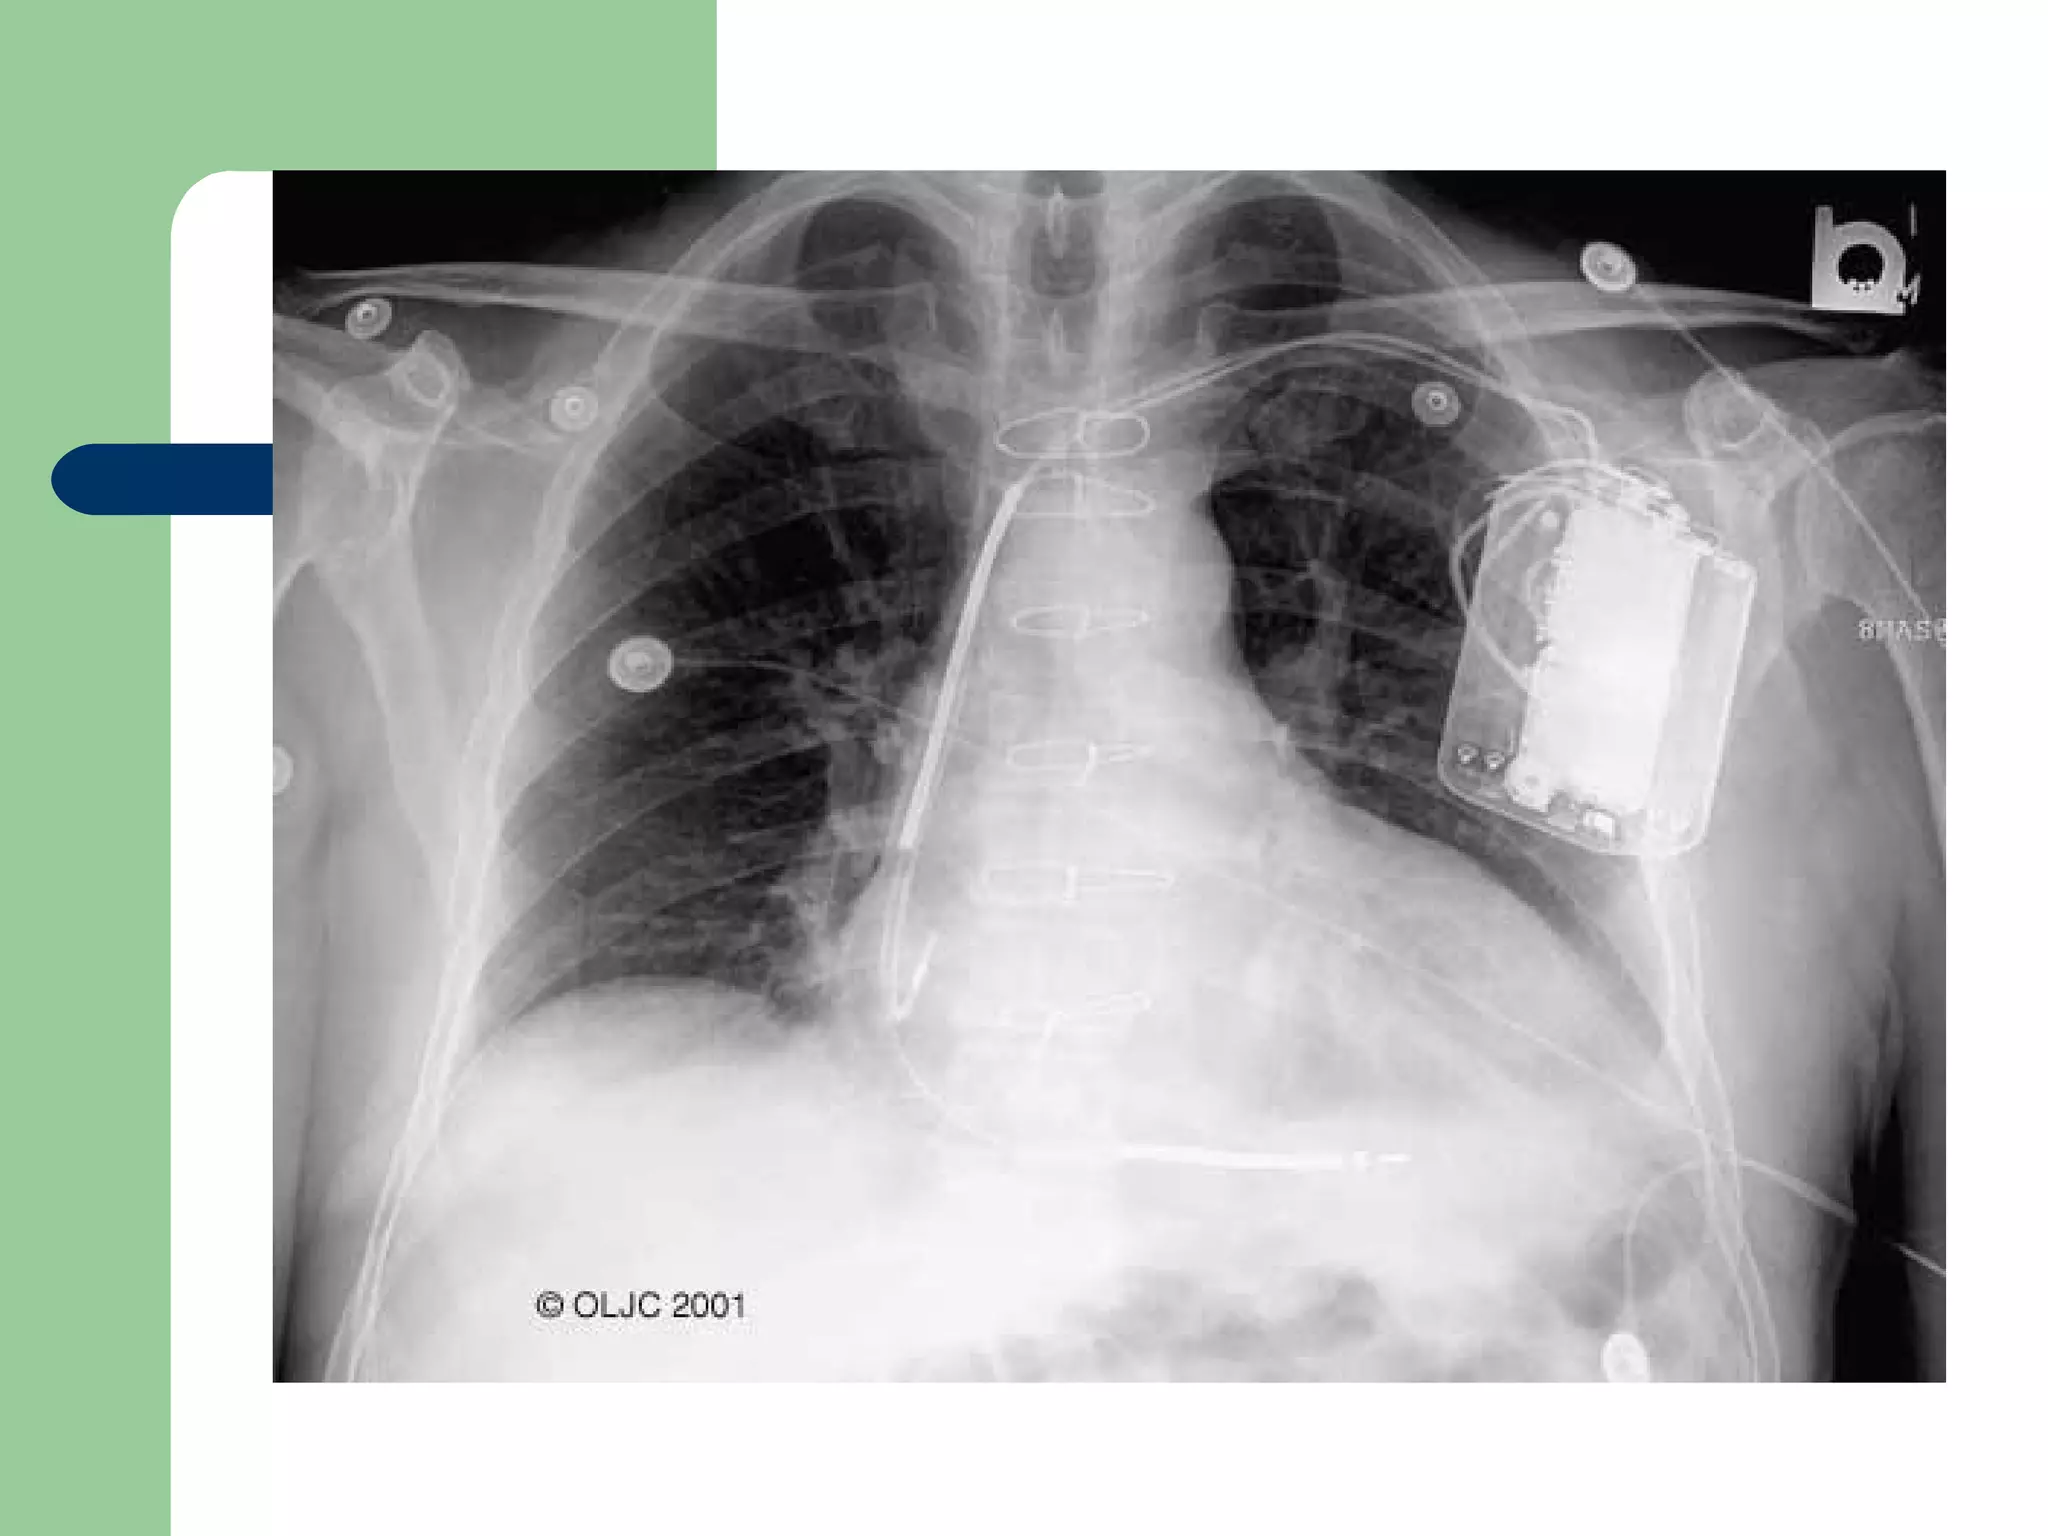

Technique of Permanent Pacing

 In permanent pacing, leads through the subclavian or cephalic

vein.

 Leads positioned in the right atrial appendage for atrial pacing

and right ventricular apex for ventricular pacing.

 The pulse generator lies in the subcutaneous pocket below the

clavicle.

 Epicardial lead placement is used when no transvenous or if

the chest is open.